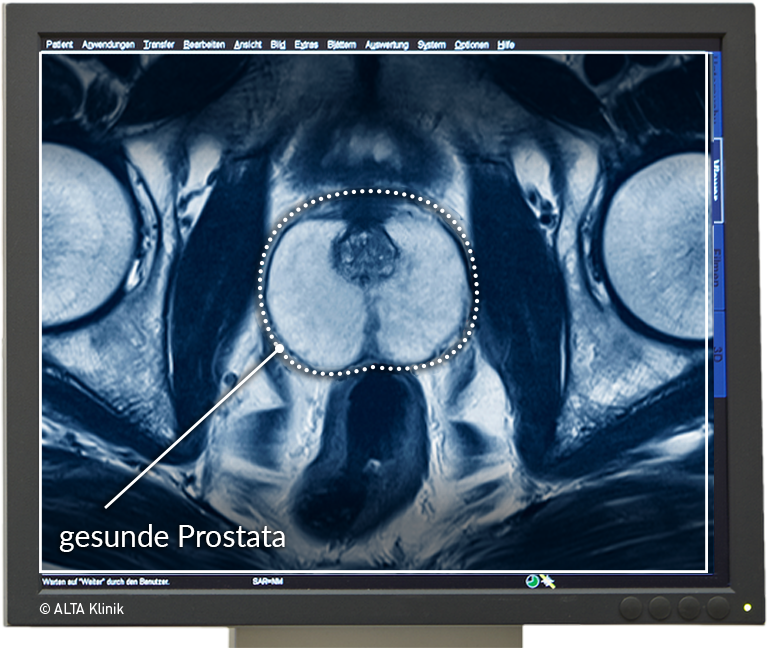

- gesunde Prostata